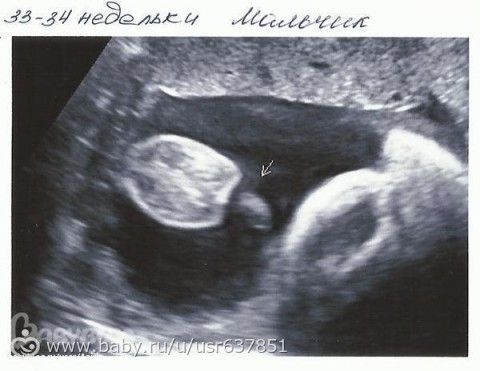

Особенности УЗИ при определении пола ребенка

Раздел: Идеи и советы